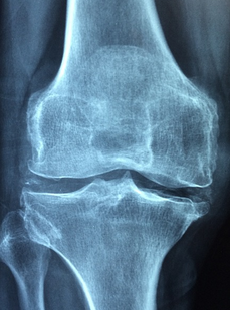

관절염 초기증상 관절염 초기증상 나타나면 대처하는 방법 등 관절염에 관한 정보 알아보도록 하겠습니다. 관절염은 관절에 염증이 생기는 질환으로, 통증, 붓기, 뻣뻣함 등의 증상을 유발합니다. 관절염은 여러 가지 원인과 유형이 있지만, 가장 흔한 것은 골관절염과 류마티스 관절염입니다. 골관절염은 관절의 연골이 닳아서 발생하는 것이고, 류마티스 관절염은 면역체계가 관절을 공격해서 발생하는 것입니다. 관절염은 조기에 발견하고 치료하지 않으면 점차 악화되어 관절의 변형이나 기능 장애를 초래할 수 있습니다

1. 관절 통증 : 관절염의 가장 대표적인 초기증상으로, 관절에 둔한 통증이나 쑤시는 통증이 있습니다. 통증은 운동이나 부하에 따라 심해지거나 가벼워질 수 있으며, 한 곳에만 있거나 여러 곳으로 옮겨갈 수 있습니다. 특히 손가락, 손목, 무릎, 발목 등의 작은 관절에 많이 나타납니다.

2. 관절 붓기 : 관절에 염증이 생기면 혈액 순환이 나빠져서 부종이 생깁니다. 부종은 관절을 만지면 따끔하거나 따뜻하게 느껴집니다. 부종은 주로 류마티스 관절염에서 많이 나타나며, 골관절염에서는 드물게 나타납니다.

3. 관절 뻣뻣함 : 관절에 염증이 생기면 관절의 움직임이 제한되고 뻣뻣해집니다. 뻣뻣함은 오랫동안 같은 자세를 유지하거나 잠자고 일어날 때 더 심해집니다. 뻣뻣함은 주로 골관절염에서 많이 나타나며, 류마티스 관절염에서는 드물게 나타납니다.